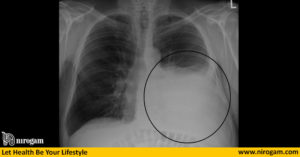

Отек легких

При отеке легких в альвеолах скапливается большое количество жидкости. Именно это и становится причиной булькающих звуков, которые нередко можно услышать и на расстоянии. К такому состоянию приводит острая сердечная недостаточность с застоем крови в малом круге. Приступ начинается остро, в ночное время или днем на фоне физической нагрузки. Удушье сопровождается следующими признаками:

- Кашель с выделением пенистой мокроты, окрашенной в розовый цвет.

- Дистанционные клокочущие хрипы (слышные на расстоянии).

- Давящие боли в грудной клетке.

- Поверхностное дыхание.

- Ослабление пульса.

- Падение давления.

Пациент принимает вынужденное положение, кожа бледнеет и покрывается липким потом, лицо становится цианотичным. Характерны возбуждение и страх смерти. При аускультации в легких определяются множественные мелкопузырчатые хрипы, ослабление дыхания. Перкуторный звук укорочен.

Когда у человека клокочет в грудной клетке, необходимо прежде всего исключить острое состояние, связанное с отеком легких.